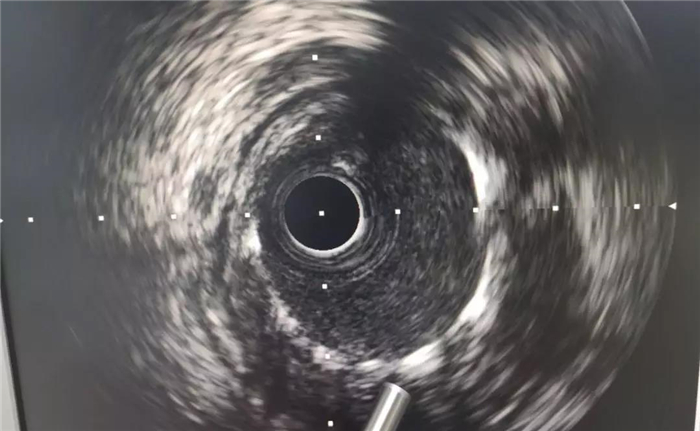

手術(shù)中,心血管病介入團(tuán)隊(duì)將患者的血栓抽出,植入支架,再經(jīng)心血管內(nèi)超聲(IVUS)檢查顯示:患者支架貼壁良好,無夾層、血腫、血栓影,前向血流TIMI3級(jí)。經(jīng)過45分鐘,手術(shù)順利完成,患者胸痛、胸悶癥狀消失,安全返回病房,患者及家屬均對(duì)這次手術(shù)給予了肯定。

血管超聲檢查支架貼壁情況